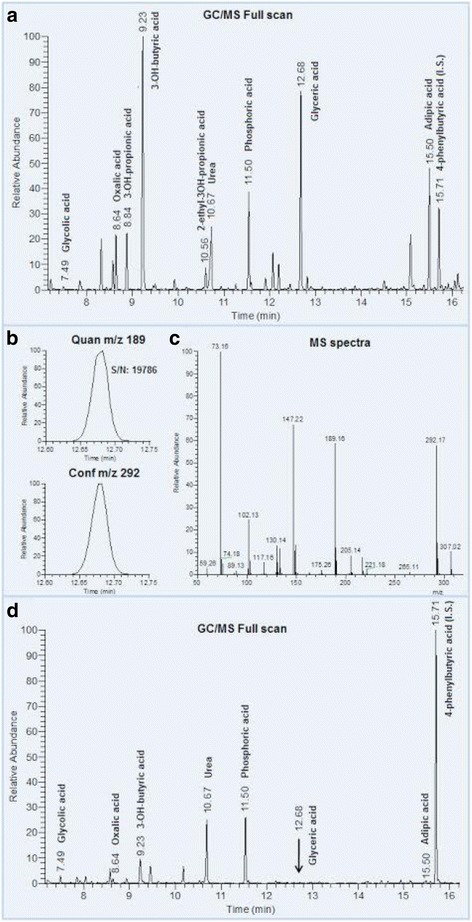

A routine GC/MS analysis of organic acids in the patient’s urine samples revealed a marked peak in/with a retention time of 12.7 min corresponding to compounds with retention index 1342 MU (methylene units). On the physiological urine chromatogram this peak is negligible. A comparison of the obtained chromatographic data with the library mass spectra (NIST library) revealed that the peak corresponded to glycerate (Fig. 2). Quantification of organic acids content in the urine uncovered clear-cut abnormalities when compared to accepted refference values.Oxalate was only moderately elevated up to 349 mmol/mol creatinine (reference age-related interval 61–162 mmol/mol creatinine). In contrast to the oxalate, the glycerate value was extraordinarily high, reaching 2796 mmol/mol creatinine (reference only trace). On the other hand, the glycolate urine excretion was normal, reaching 69 mmol/mol creatinine (reference interval 22–139 mmol/mol creatinine). The finding of extremely high glycerate excretion was crucial for the choice of gene responsible for methabolic pathology and molecular genetic diagnostic. In addition to this principal metabolic finding, we found increased excretion of 3-hydroxybutyrate (HBA; 605 mmol/mol creatinine), 3-hydroxyisobutyric acid (HIBA; 80.2 mmol/mol creatinine), and adipate (134 mmol/mol) in the examined urine sample - all typical marks of ketosis. In comparison to the control samples, two trace metabolites 3-hydroxypropionic acid (HPA, alternative name hydracrylate) and 2-ethyl-3-hydroxypropionic acids (EHPA; alternative names: 2-hydroxymethyl-butyrate, 2-ethylhydracrylate) were also substantially elevated in the urine. The quantity of HPA was estimated by an obligatory procedure based on the comparison of ion areas (Q-177) of the patient's sample, and HPA standard and revealed value 593 mmol/mol creatinine. Due to the absence of a commercially available standard, EHPA quantification was performed using arbitrary units (ratio of metabolite area to area of standard). According to data from the Human Urine Metabolome Database, the average value of EHPA is 4 mmol/mol creatinine, and based on this finding and data from our control samples we estimate that the excretion of EHPA may be approximately 40 mmol/mol of creatinine in the patient’s urine sample. In the chromatogram we observed an unknown metabolite at a retention time corresponding to 1500 MU.

Fig. 2.

GC/MS chromatogram of urine organic acids of patient with PH2 and control sample. a The total ion current chromatogram of urine organic acids of patient sample with markedly elevated peak in retention time 12.68 corresponding to glyceric acid (MU-1342). b The presence of two characteristic ions for glyceric acid with high signal to noise ratio (S/N) for quantitative ion in patient’s sample. c MS spectra of peak corresponding to glyceric acid. d The total ion current chromatograph of urine organic acids of control sample with negligible peak of glyceric acids

The measurement of urine organic acids level in the patient’s second sample (five days after surgical intervention) confirmed increased values of oxalate and glycerate (167 mmol/mol and 1113 mmol/mol creatinine respectively), however, normal values of HBA and adipate were observed. Furthermore, the excretion of BAIB acid returned to the physiological level (27 mmol/mol creatinine). As for HPA and EHPA, while the EHPA levels decreased to normal, the excretion of HPA remained significantly elevated. The unknown metabolite observed in the first sample was not detected in this urine sample. In order to interpret the observed secondary metabolic changes correctly, we decided to compare the increase in the urine excretion levels of all the mentioned metabolites with the control samples and the samples of ketonuric patients obtained from our database (Table 1). We used values of 11 control samples of probands of both genders and aged more than 6 months.